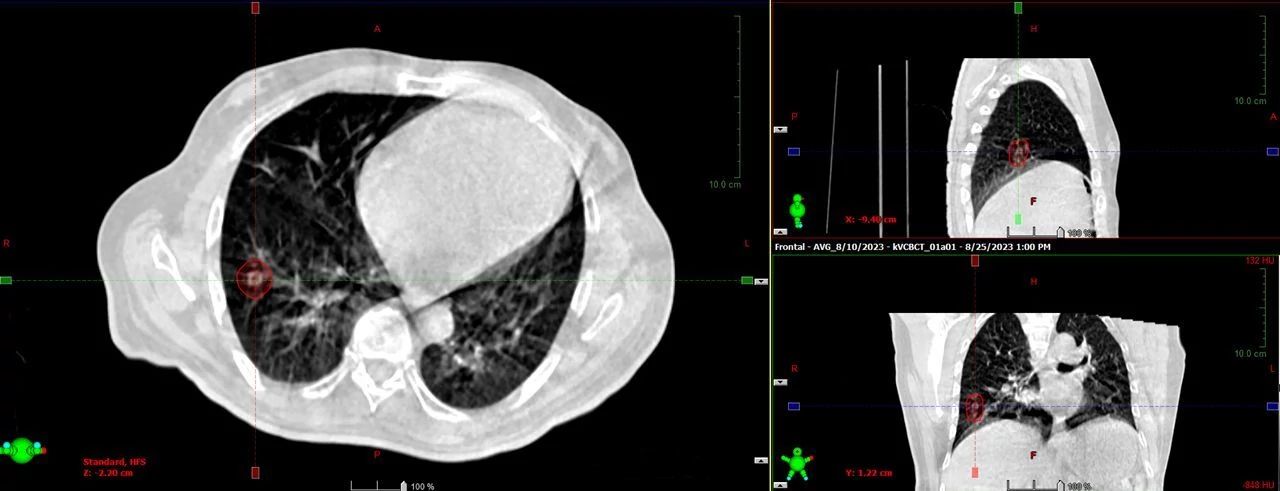

HyperSight brings fast, highly accurate imaging into the treatment room. It enables the acquisition of cone-beam CT (CBCT) images in as little as six seconds, with the Hounsfield Unit (HU) accuracy required for calculating dose distributions directly on the images. The HyperSight image reconstruction algorithms, combined with the expanded field of view (FOV) offer improved visualization of larger areas of interest often encompassing the entire target volume and surrounding organs at risk (OARs). HyperSight is now available as an optional feature on Varian’s Halcyon, Ethos, TrueBeam, and Edge radiotherapy systems.

According to Wesley Talcott, MD, MBA, radiation oncologist at Lenox Hill Hospital, HyperSight, and the high-resolution images it can generate, enable him to tighten margins and treat more challenging cases. “HyperSight allows us to potentially offer treatments to patients who may be more challenging to treat,” he says, citing the case of patients who would otherwise require very large margins that could increase toxicity, patients requiring a larger field of view, and abdominal patients with bilateral hip implants. “I don’t want to say that it would be impossible to treat these patients but treating with support from HyperSight imaging certainly gives us more confidence.” Because the high-fidelity imaging has the potential to make more treatment options available to physicians and patients, Dr. Talcott looks at HyperSight as an appealing differentiator in the Manhattan area.

HyperSight images show how radiotherapy treatment and physiological processes such as weight loss are impacting the tumor and surrounding anatomy over a course of treatment. The enhanced-quality HyperSight CBCT images generated right in the treatment vault make it possible to more easily compensate for any changes to the tumor and nearby organs. Previously, processes for adapting to such changes often required a new CT scan on a separate machine.

Clinicians at Icon Cancer Centre Holmesglen also use HyperSight imaging to streamline replanning decisions for patients on treatment. “When we see changes in volumes or contours, we are able to quickly run a calculation on the CBCT showing dose distributions for quicker decisions about whether to go ahead and treat or to stop and rescan,” says Sarah Hauville, Radiation Therapy Manager.